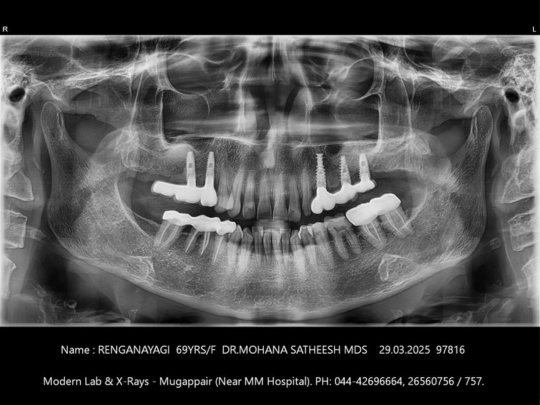

Implant

Before and After